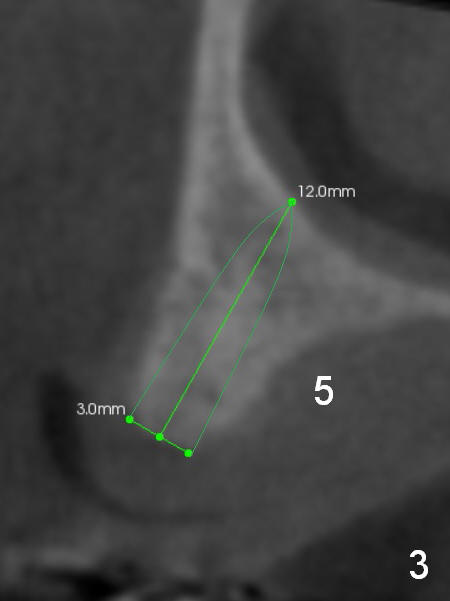

A 69-year-old man would consider implant option for his upper front teeth (Fig.1: #5-9) if there is no separate bone graft procedure. He does not want implants for his lower left molars (#18,19), since he has had a partial denture. In fact the bone at #5-9 is so thin that 2-3 mm 1-piece implants can be placed at #5,7 and 9 (Fig.2-5 (CT coronal sections (B: buccal)) for a 5-unit bridge (Fig.1). To support and increase the longevity of the latter, implants at #18,19 are mandatory (Fig.6,7).